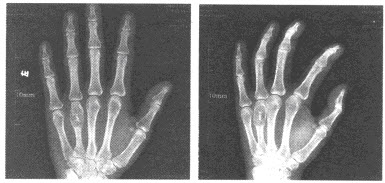

27、单项选择题

出生6个月的男婴,摔地后右手红肿,结合CR片,正确的骨折类型是()

A.青枝骨折

B.横行骨折

C.斜行骨折

D.粉碎性骨折

E.压缩骨折